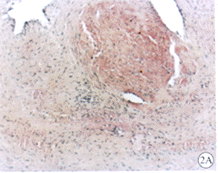

2.3 血管组织切片显微镜下观察 (1)对照组:内膜极度增厚,几乎堵塞管腔,可见附壁血栓。新生内膜主要由血管平滑肌细胞、炎性细胞、纤维母细胞和大量细胞间质构成(图2A,B;图见插页)。(2)实验组:内膜增生较对照组明显减轻,新生内膜主要成分为血管平滑肌细胞及胞外基质,远端流出道吻合口内膜增生又较近端流入道明显减轻。移植的静脉片段中膜明显增厚,且有发达的内弹力膜,呈动脉样结构改变,少量的平滑肌细胞呈泡沫样改变,未见脂纹和胆固醇结晶(图2C,D,图3A,B;图见插页)。

图2 吻合口动脉内膜增生情况

Fig 2 Anastomotic intimal hyperplasia

A: Control group (HE×10); B: Control group (V/G×10); C: Experimental group(HE×10); D: Experimental group (V/G×10)